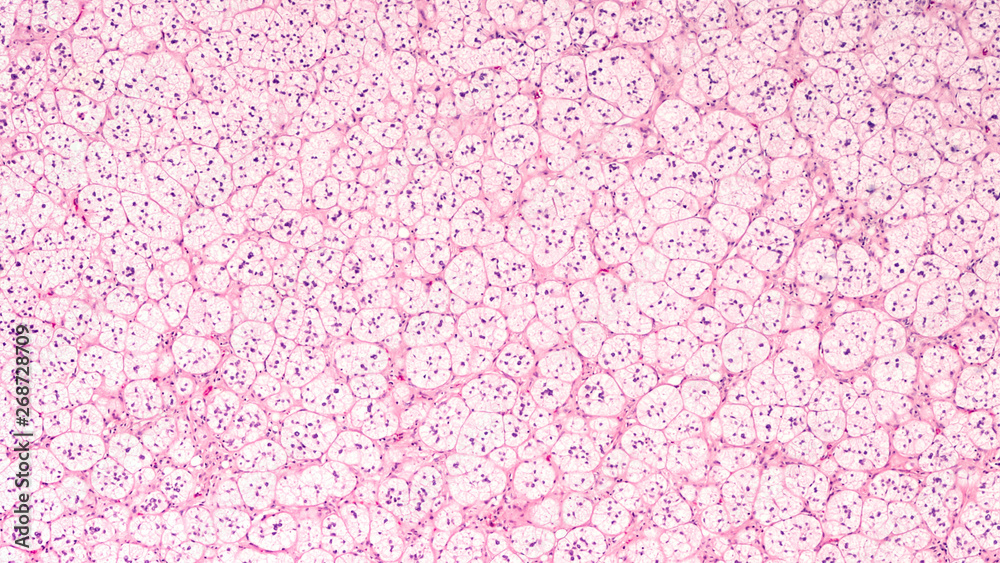

Microscopic image of an adrenal cortical adenoma, a benign tumor of the What Is Adrenal Cortical Adenoma May or may not be functional. an adrenal adenoma is a benign tumor that can form in your adrenal glands. an adrenocortical adenoma or adrenal adenoma is commonly described as a benign neoplasm emerging from the cells that. benign adrenal tumors that grow in the cortex are called adrenal adenomas. Those that grow in the medulla. . What Is Adrenal Cortical Adenoma.

Adrenal cortical adenoma histopathology showing characteristic tumour What Is Adrenal Cortical Adenoma Benign neoplasm arising from adrenal cortical cells. Most adrenal adenomas are typically discovered. benign adrenal tumors that grow in the cortex are called adrenal adenomas. definition / general. Those that grow in the medulla. an adrenal adenoma is a benign tumor that can form in your adrenal glands. an adrenocortical adenoma or adrenal adenoma is commonly. What Is Adrenal Cortical Adenoma.

Adrenal cortical adenoma with areas of focal necrosis. Download What Is Adrenal Cortical Adenoma Located right above your kidneys, the adrenal glands play a crucial role. definition / general. an adrenal gland adenoma is a tumor on your adrenal gland that isn’t cancer, but can still cause problems. adrenal adenomas are benign neoplasms that originate from the adrenal cortex. May or may not be functional. an adrenocortical adenoma or adrenal. What Is Adrenal Cortical Adenoma.